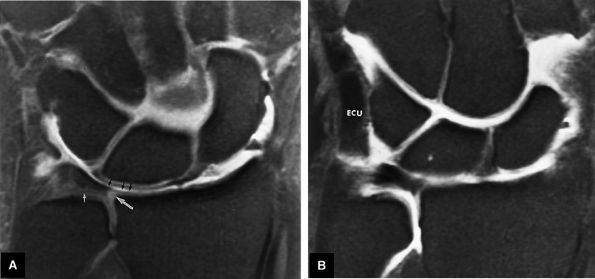

FIGURE 10.74 ● Membranous wedge-shaped component of the scapholunate ligament with direct proximal attachment to the articular surfaces of the scaphoid and lunate. The distal apex is free without direct attachment and presents as a prominent distal protrusion into the scapholunate articulation. (A) Coronal color illustration. (B) Coronal FS PD FSE image.